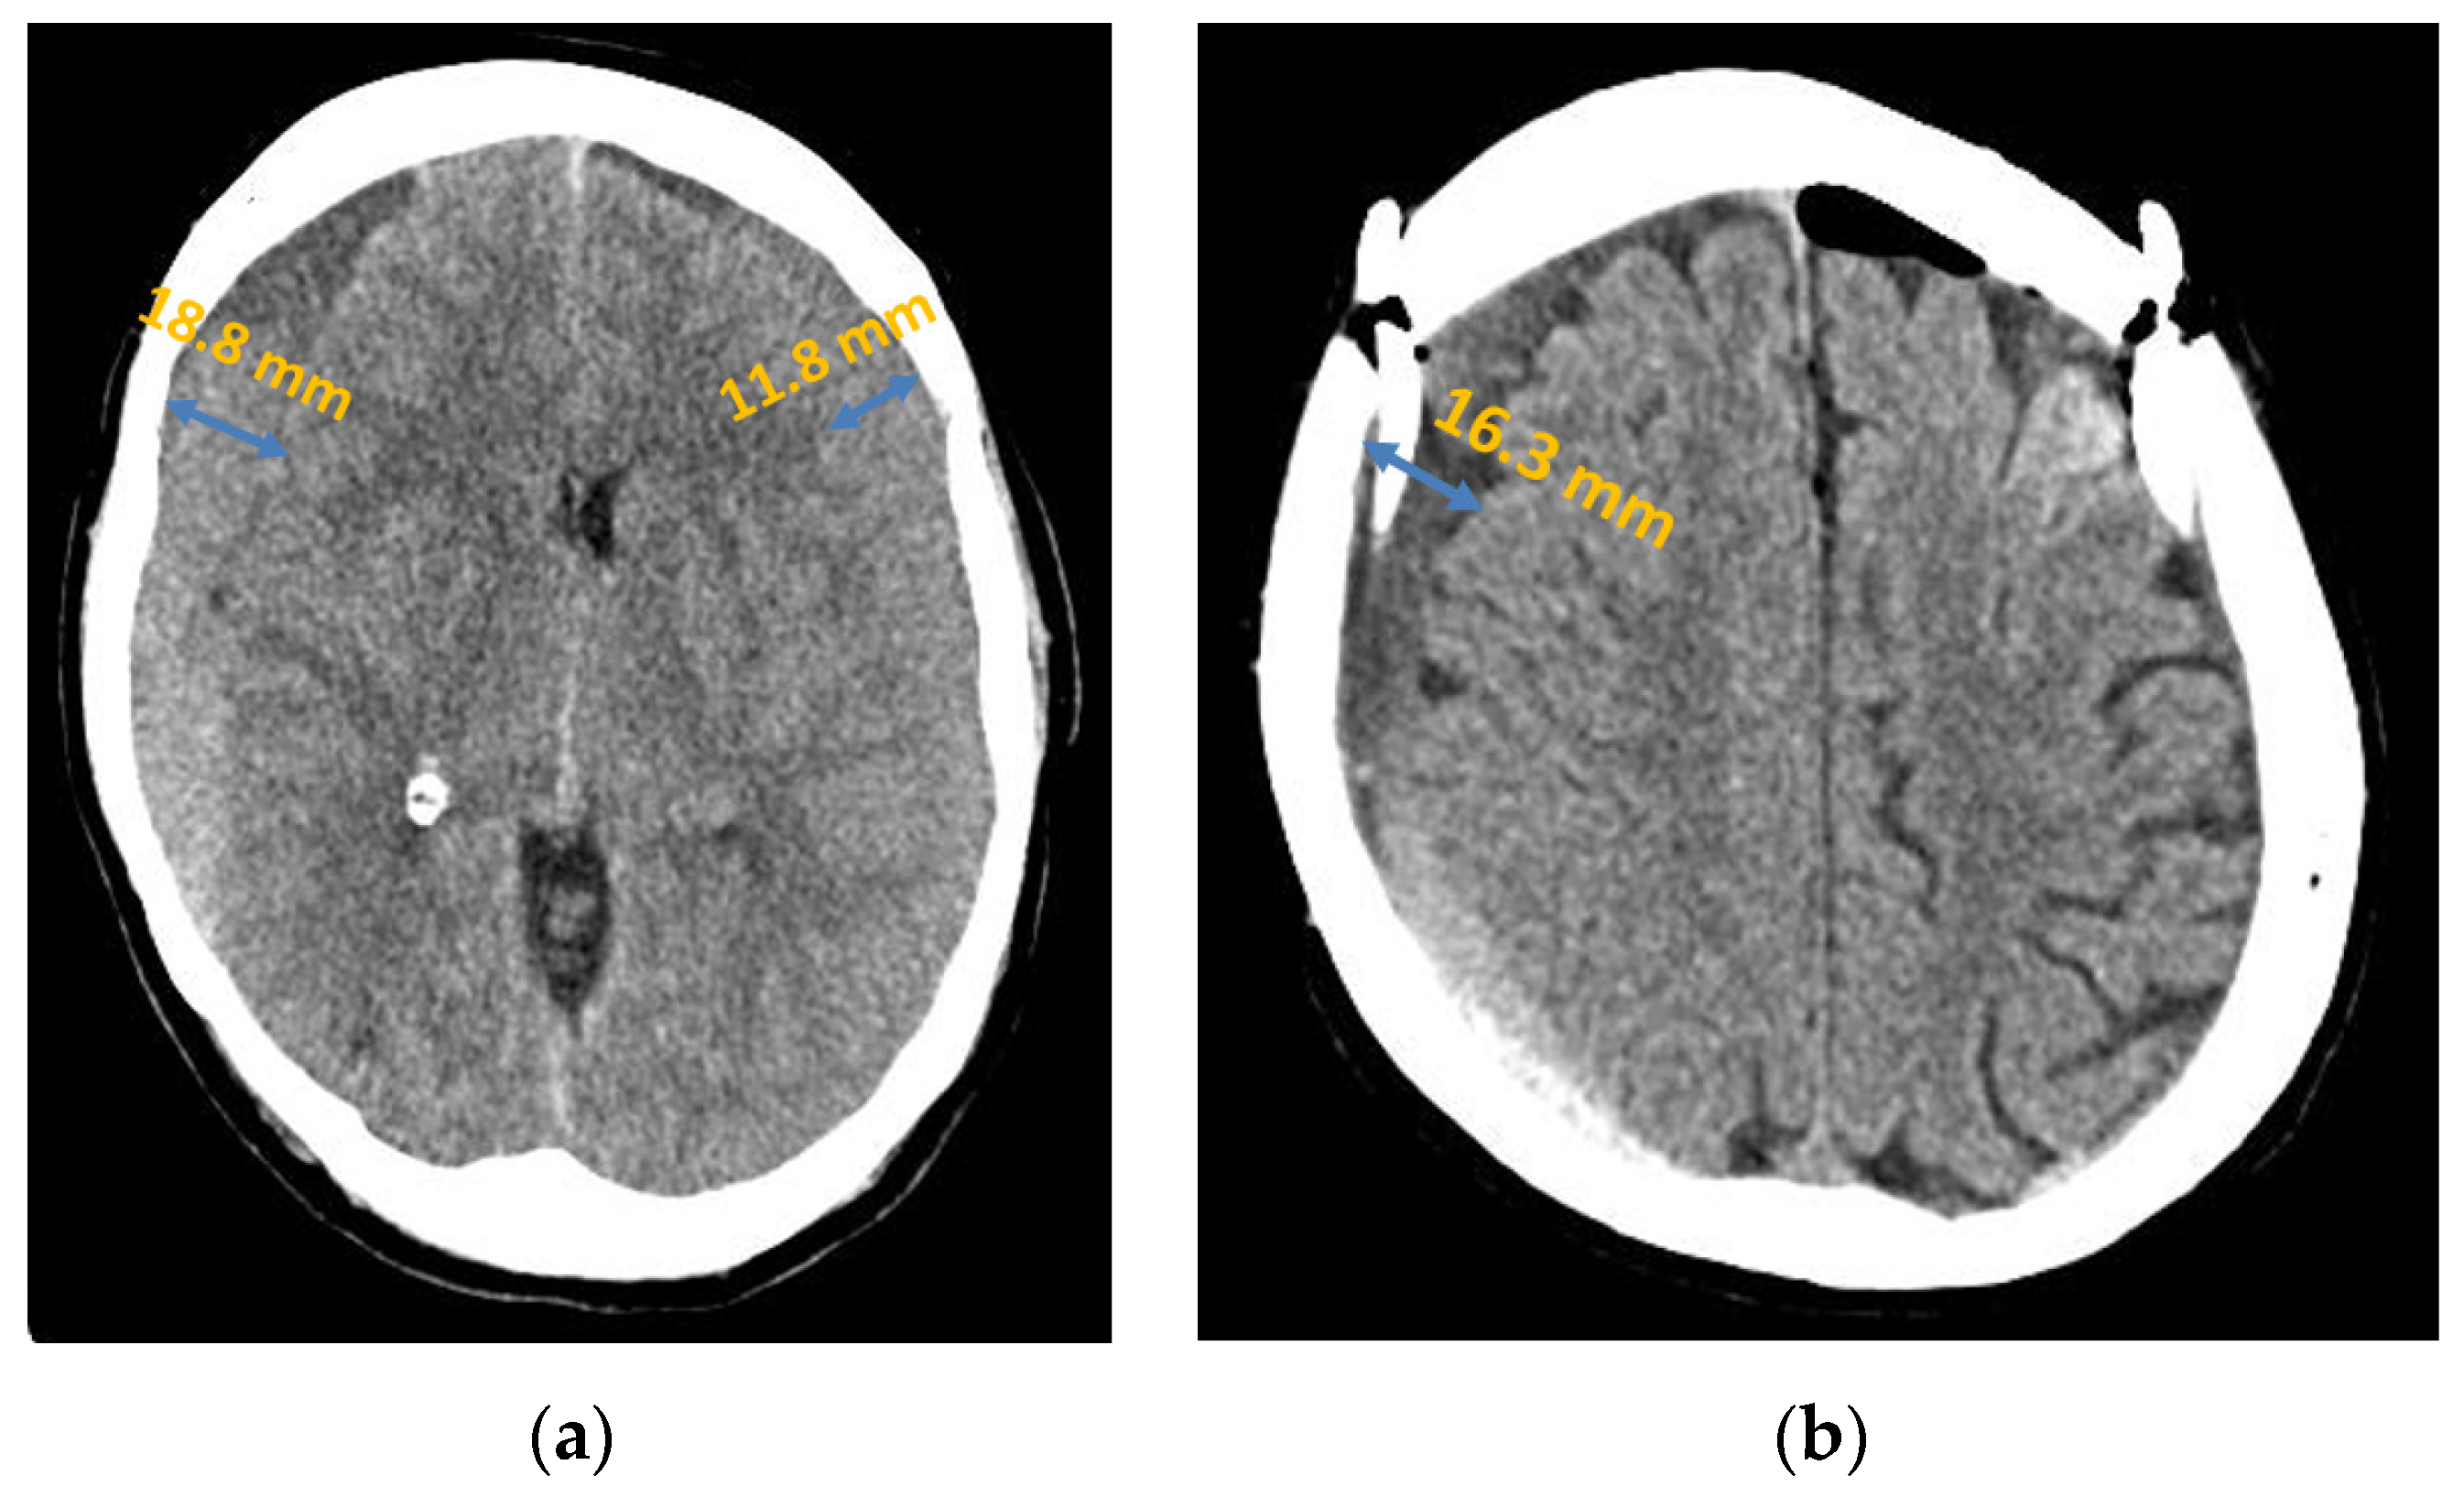

Considering the entire patient collective, the chronic subdural haematoma extended in most cases (45.56%, n = 41) over the entire affected hemisphere or over both affected hemispheres; see Figure 2. The second most common localisation was fronto-parietal localisation in 28.89% (n = 26), followed by frontal localisation in 16.67% (n = 15). This distribution followed the same order in both patient groups.

Figure 2.

Chronic subdural haematoma extended over both hemispheres: (a) preoperative presentation in axial CT; (b) postoperative presentation in axial CT.

In the patient group in which a recurrence occurred, the subdural haematoma extended over the entire affected hemisphere in 56.57% (n = 17), the fronto-parietal localisation in 33.33%, (n = 10), and the frontal localisation in 10.00% (n = 3). In the group of patients without a recurrence, 40.00% (n = 24) showed an extension over the entire hemisphere (16.56% lower than in the recurrent group of patients), 26.67% (n = 16) the fronto-parietal localisation, and 20.00% (n = 12) the frontal localisation. Furthermore, in two cases (3.33%), there was a parietal localisation and in one case (1.67%) a parieto-occipital localisation (Figure 3). However, the Fisher–Freeman–Halton exact test showed localisation was not a statistically significant prognostic factor for the risk of recurrence (p-value = 0.28).